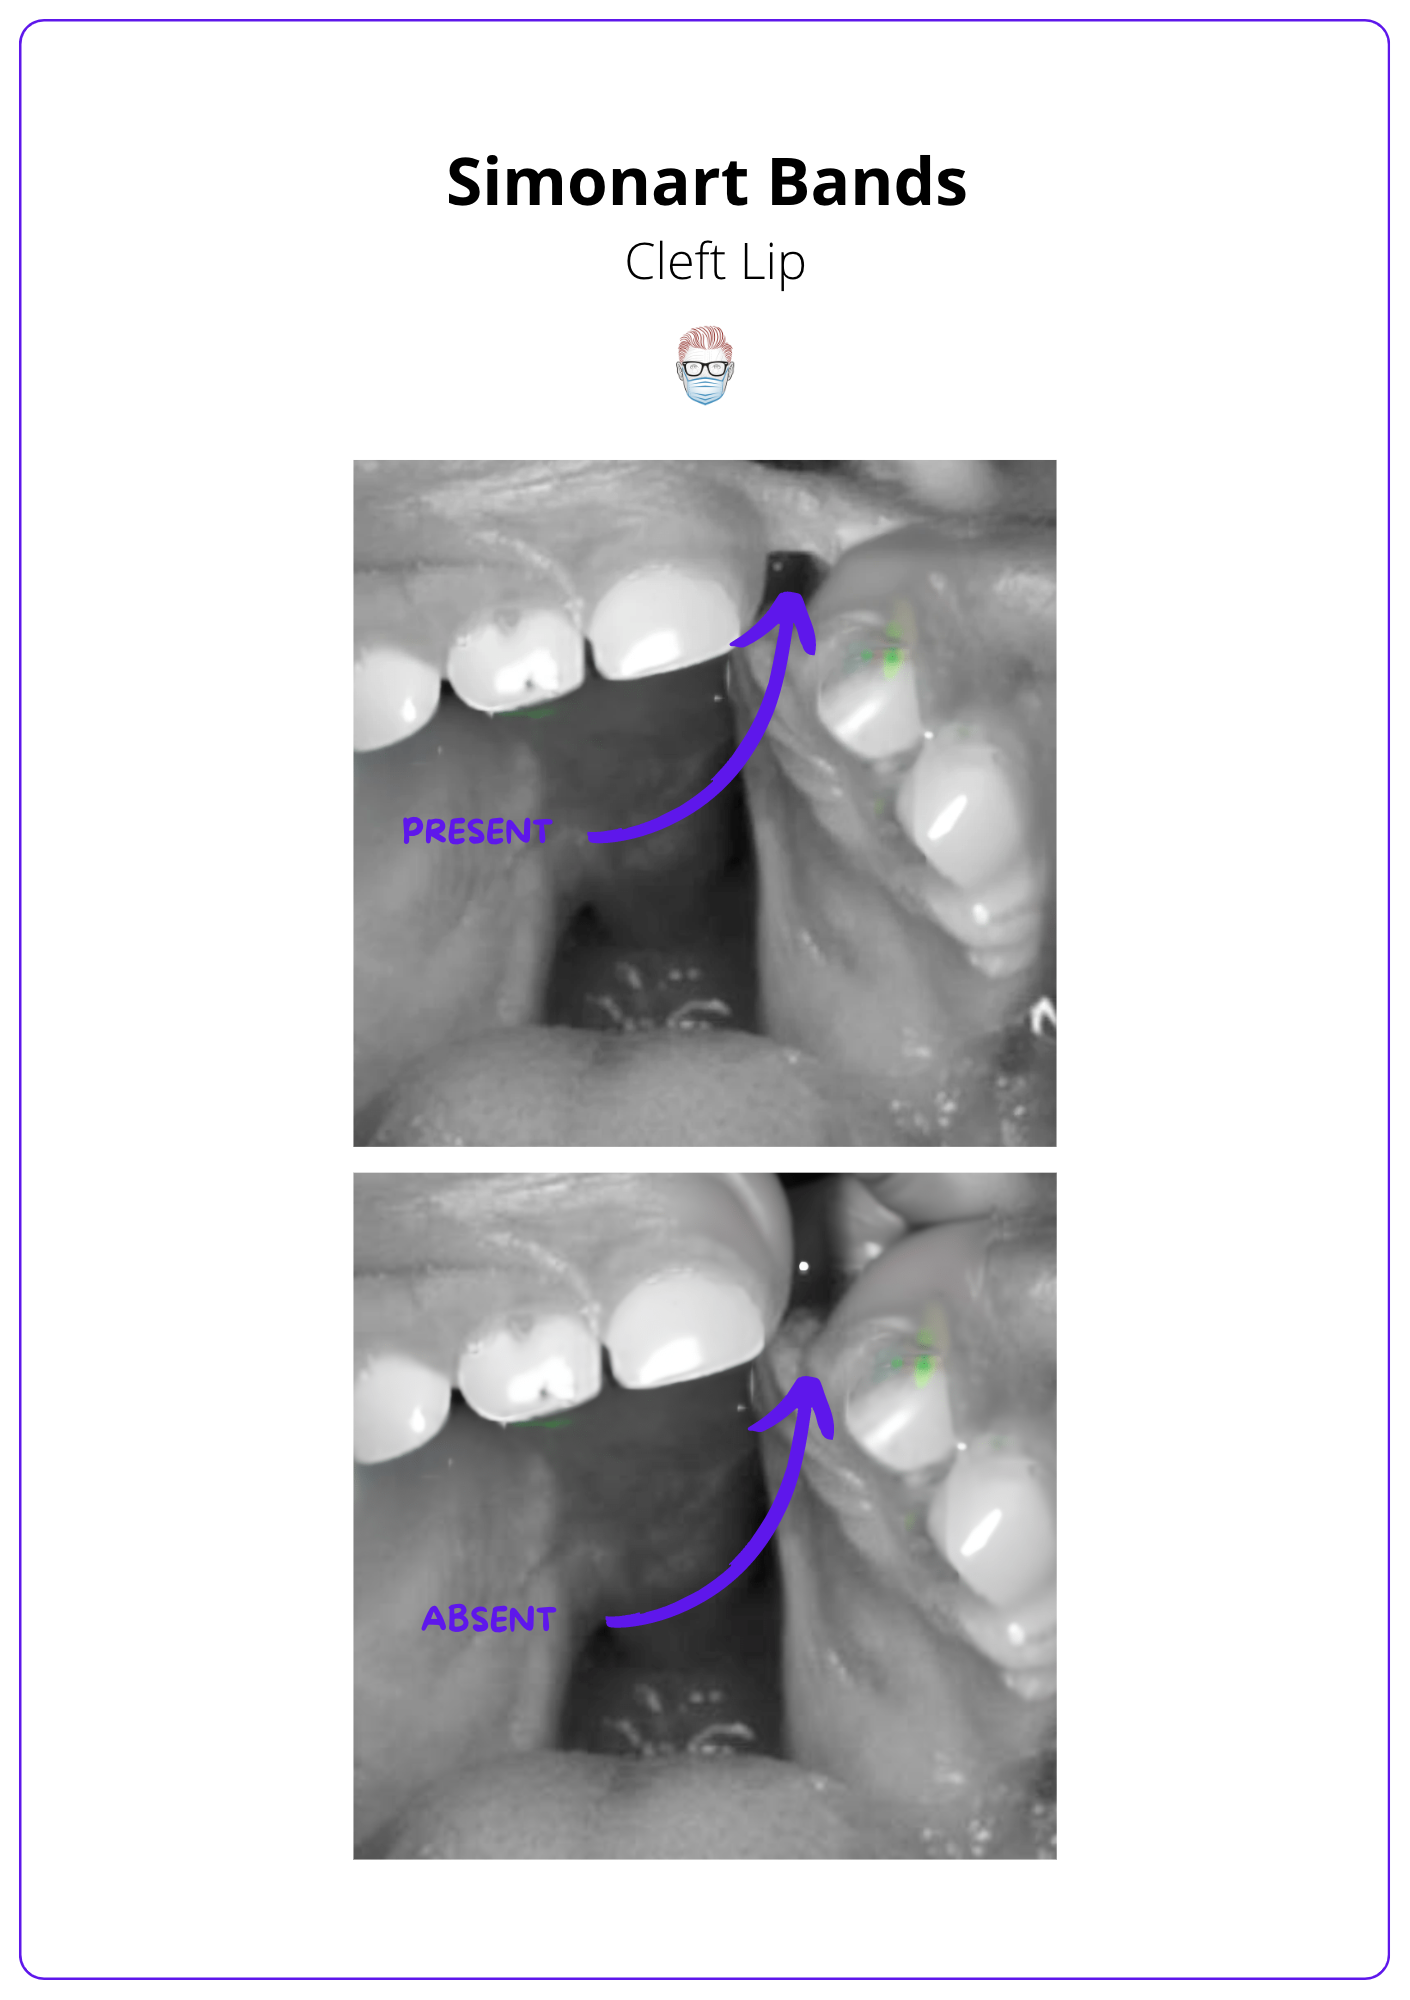

- Simonart Band: a fibrous tissue bridge that may partially connect the edges of a cleft lip or palate. It does not contain any muscle and does not convert a complete into an incomplete cleft lip.